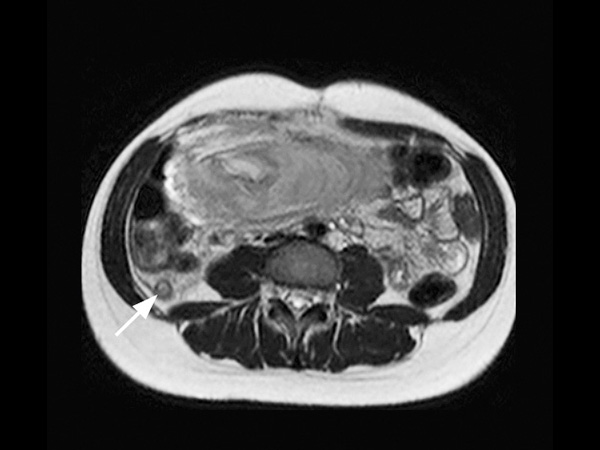

A 25-year-old female, 20 weeks pregnant, presented with right lower quadrant pain. Her white blood cell count was elevated, measuring 14.6. Ultrasound failed to visualize the appendix. Consequently, the patient was referred for MRI. The scan was performed on a 1.5T SmartPath to dStream system using the integrated Posterior coil and the Anterior coil. The exam includes 3-plane T2-weighted scans, 3-plane B-FFE scans and axial T2W SPAIR, all in breath holds < 15 seconds. The MR images demonstrate a distended appendix with adjacent fat stranding. The diagnosis is acute non-perforated retrocecal appendicitis, surgically confirmed. MRI successfully diagnoses appendicitis in pregnancy without using ionizing radiation or contrast. This 18-minute exam without contrast or ionizing radiation has replaced CT in pregnant women at our institution. We have performed over 60 cases in the last 5 years, with 9 positive, surgically confirmed. We saw no false positives, and to the best of our knowledge, no false negatives either. We usually start with ultrasound, but it is frequently negative in these patients. T2-weighted sequences are the mainstay for our diagnosis. With our SmartPath to dStream system, SENSE and dStream allow us to acquire these faster with improved signal. In these patients, who are often short of breath, the scan can be completed in 15 minutes or less.

Axial T2w TSE